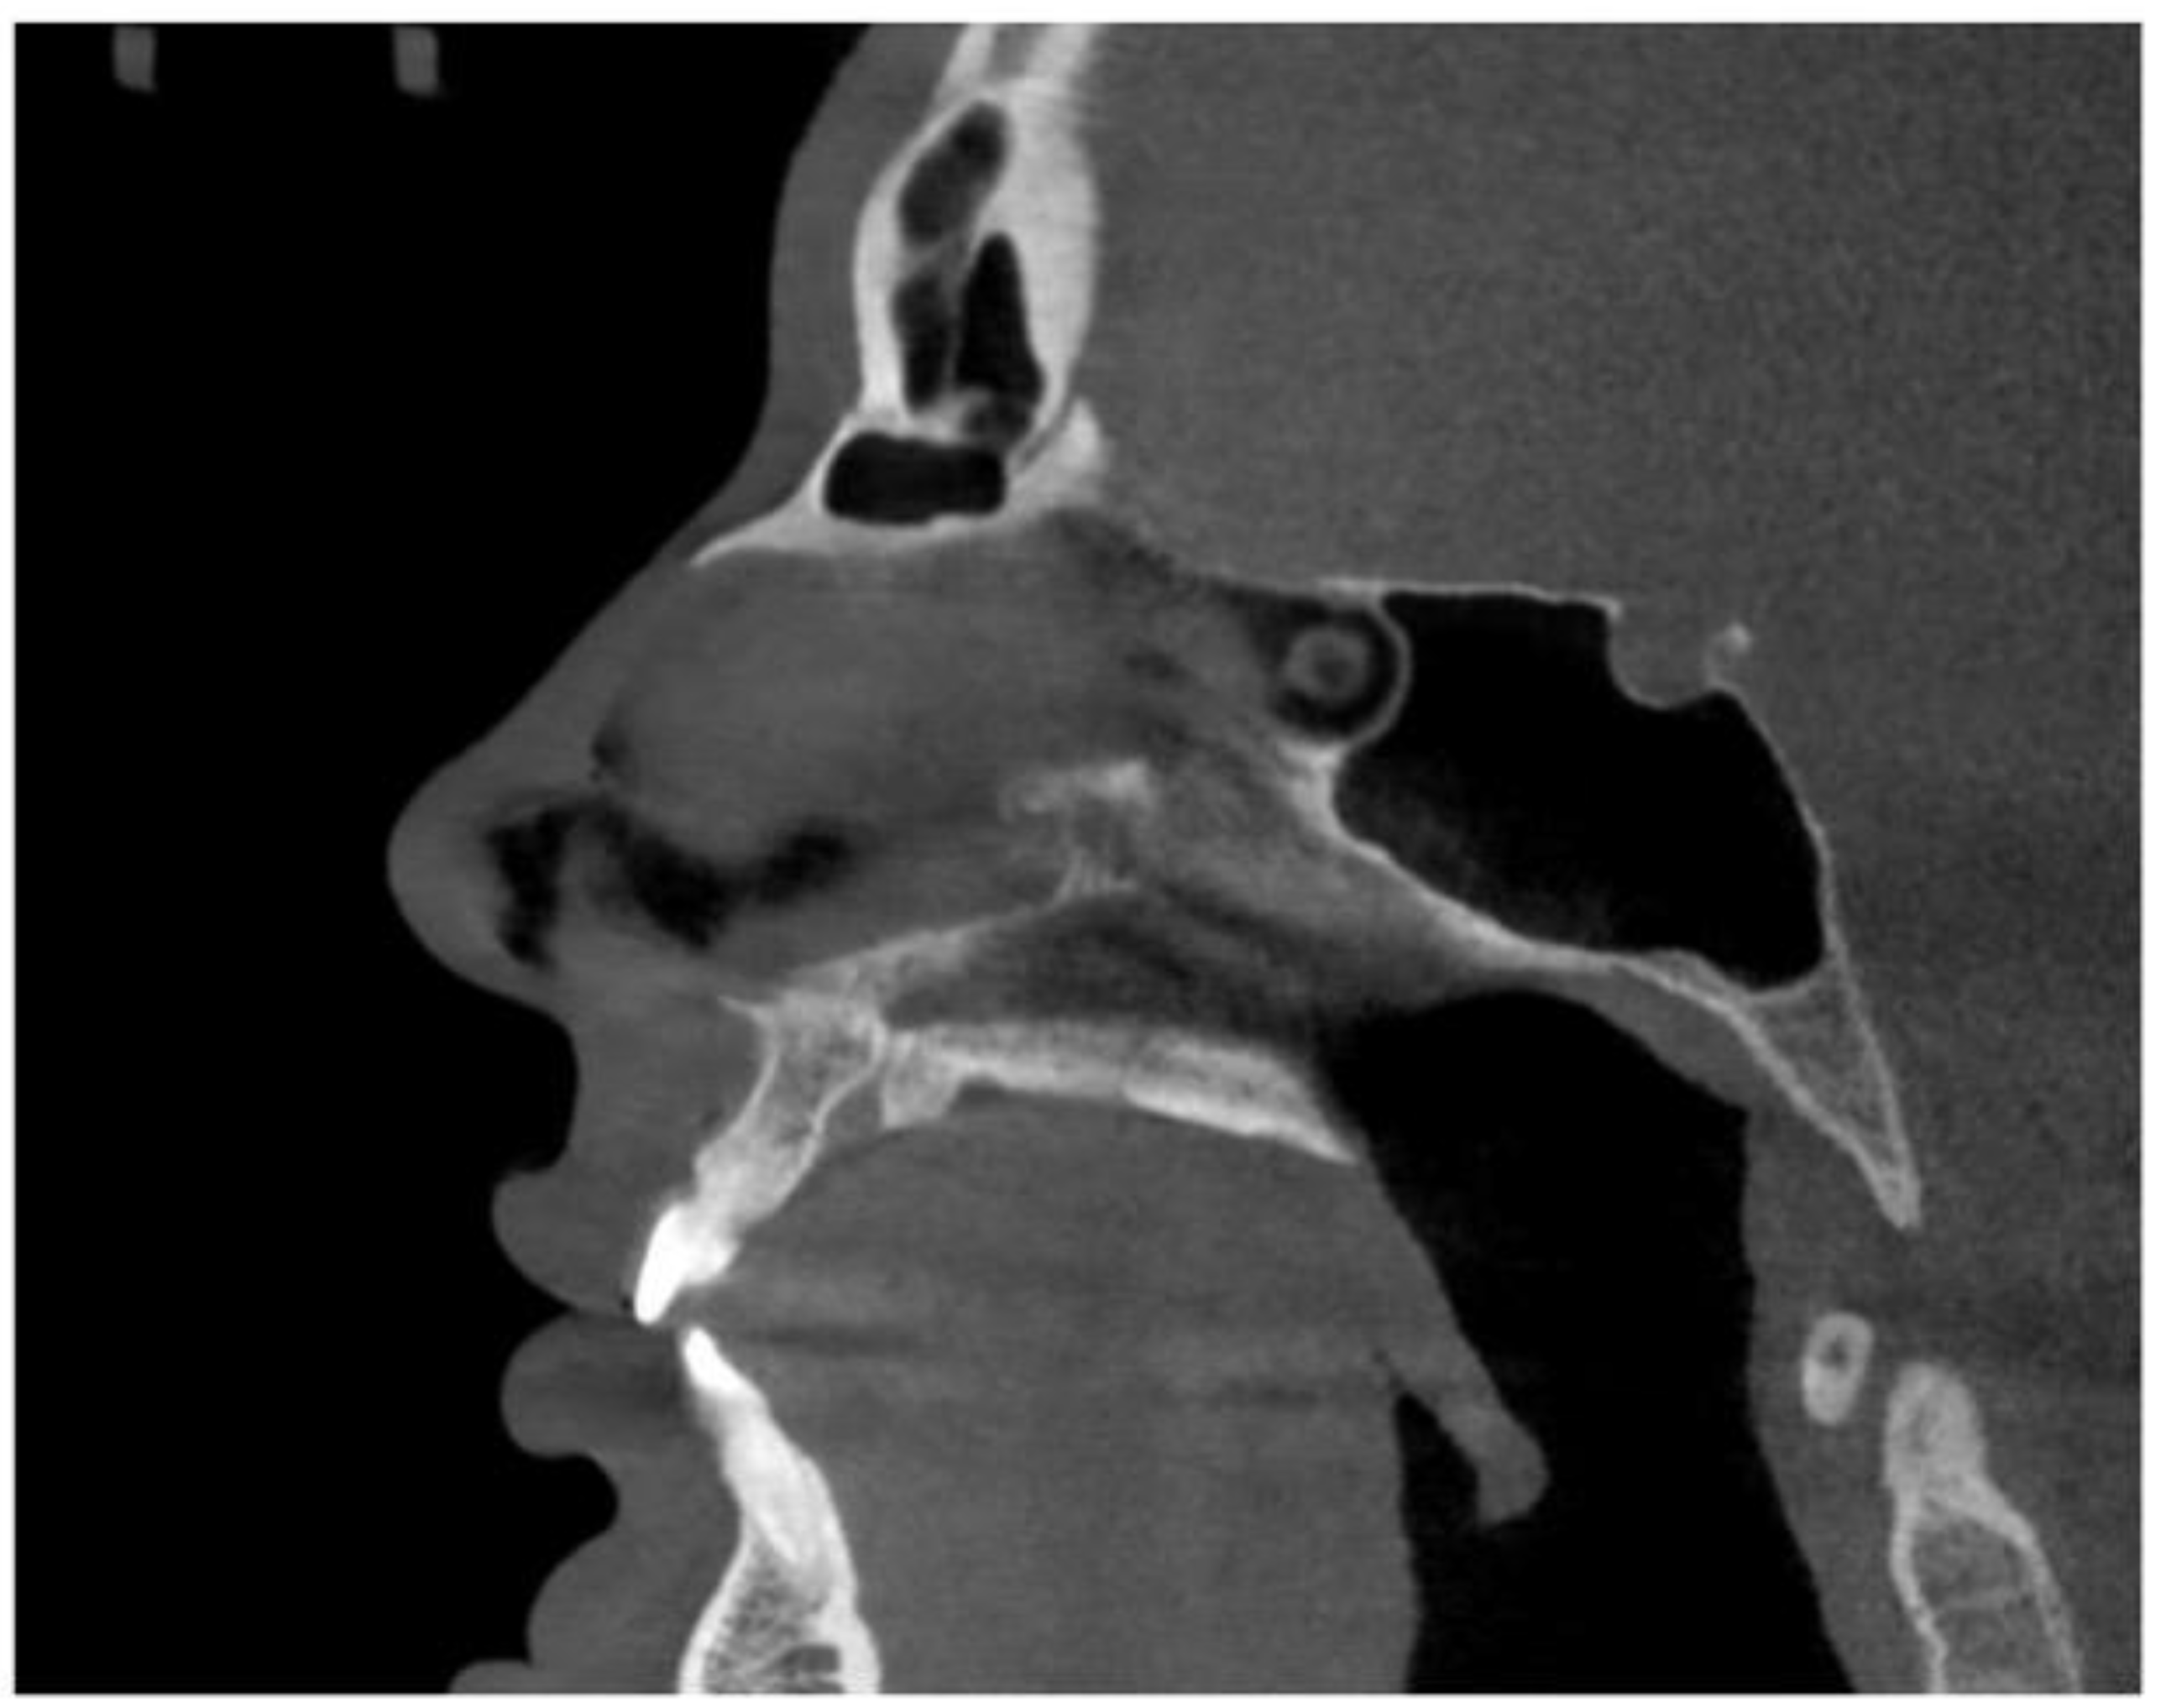

2.7. Case D: Midfacial Asymmetry Correction with Guided Expansion